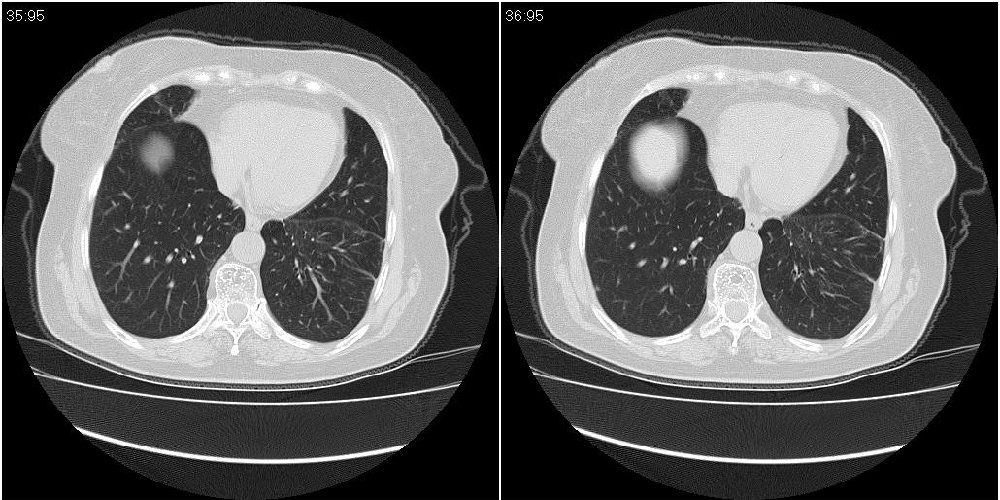

女性,72岁。去年9月份发现肺部病变,诊为肺结核并进行正规治疗至今,但复查后发现ct表现几乎没有变化。

双肺继发型tb并右中叶内膜tb,轻度支扩,左下胸膜肥厚粘连。

双肺继发性肺结核并右肺中叶节段性肺不张,左下胸膜肥厚粘连。

右肺中叶节段性肺不张,考虑结核或慢性炎症,建议做纤支镜检查。